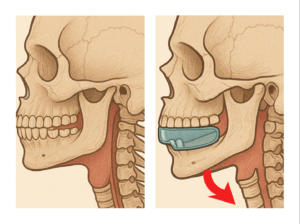

当然ながら厚みがあると下顎骨は後方に向かって回転してしまいますね。。。。

そしてこの下顎の後方回転(後退)を助けているのは

このように「後むきの」筋肉たちなのです(PTさんはこの辺り詳しいと思います)

本来MRC矯正は顔(あご)を前に向かって成長させて気道を大きくしたいのですから、これでは真逆の力が加わることになりますね。。。。

でもシステムで対応していればこのネガティブ要素を払拭できるのです!

だから。。。。マイオブレイスを渡して「噛めば治るよ〜〜〜」って言ってる先生のお話を鵜呑みにしてると顎は後退してしまう傾向が出ますので、かえって気道が狭くなってしまい、それに伴い姿勢までが悪くなってしまう可能性が高まるのです